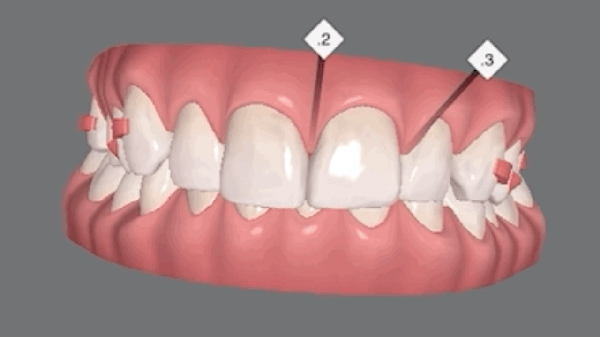

- Invisalign Express, a short-term orthodontic system designed to finish treatment within about 2–3 months.

The patient chose Invisalign Express, since it could achieve her desired results quickly without permanently altering her natural teeth.

Because she had a previous experience of quitting orthodontic treatment, she preferred an option that would not take long or cause discomfort. Once she learned that Invisalign Express could correct her smile discreetly within just a few months, she felt relieved and excited.